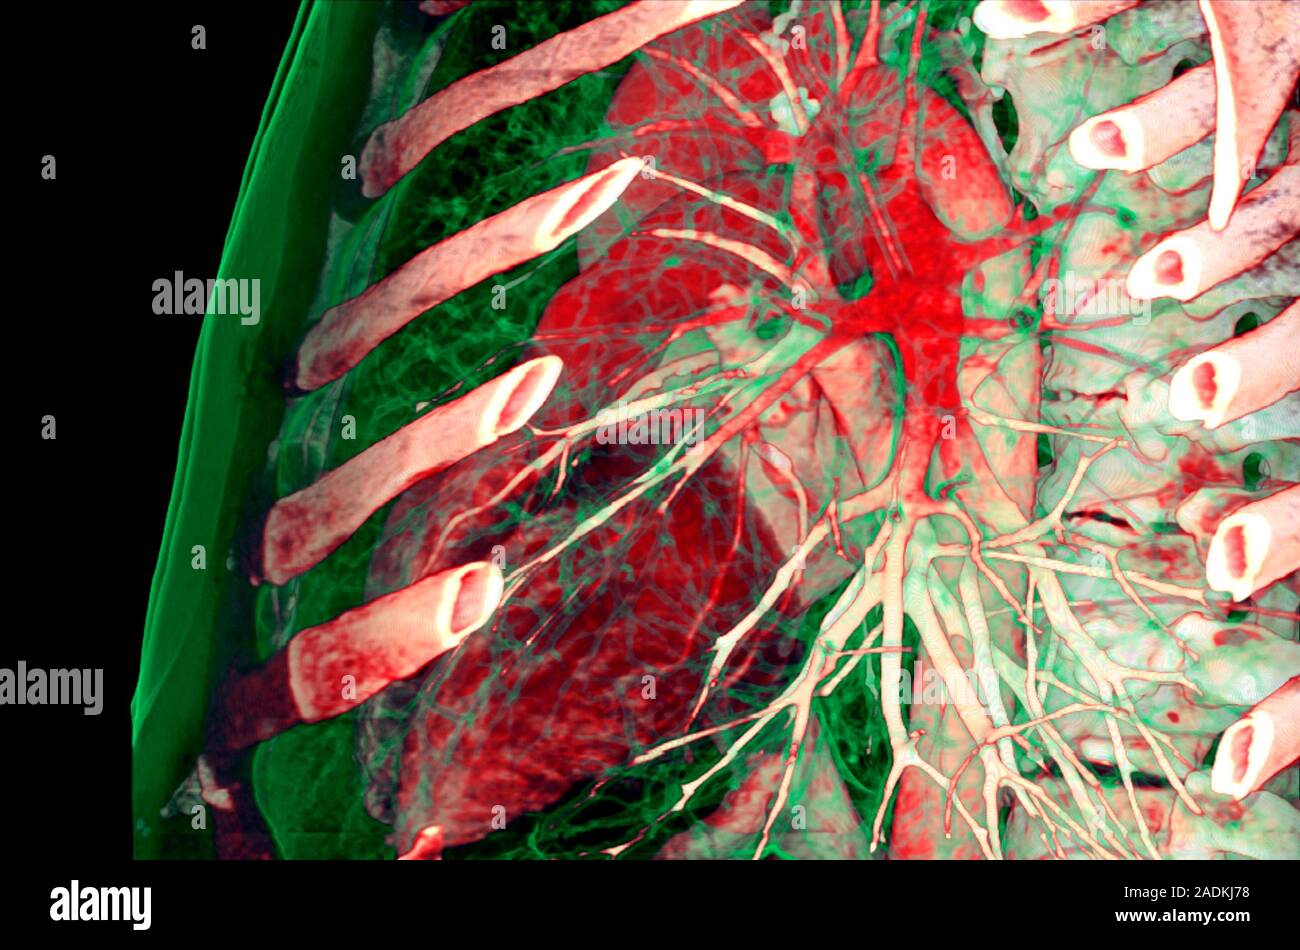

From www.alamy.com

Chest, CT scan. Coloured 3D computed tomography (CT) scan of a chest What Organs Show Up On A Chest Ct Scan Chest ct scans provide a comprehensive view of the lungs and different types of structures surrounding the lungs, heart and chest cavity, including bones, tissue and blood vessels—all in a single image. This imaging test can help your doctor diagnose a number of different lung diseases and conditions, including: Learn how to interpret ct scan results and understand what the. What Organs Show Up On A Chest Ct Scan.